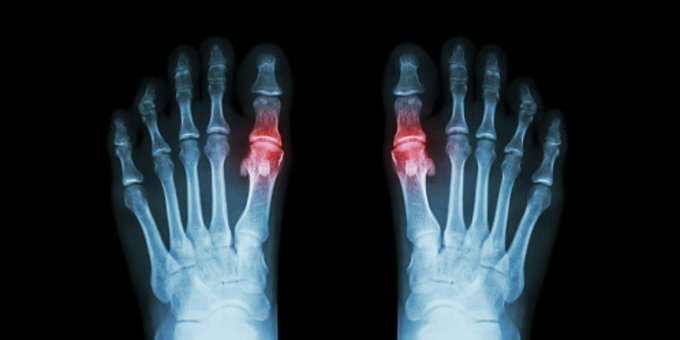

La gota es una forma común y dolorosa de artritis. Produce hinchazón, enrojecimiento, calor y rigidez en las articulaciones. Aquí lo que debes saber ow.ly/2So350AedZf